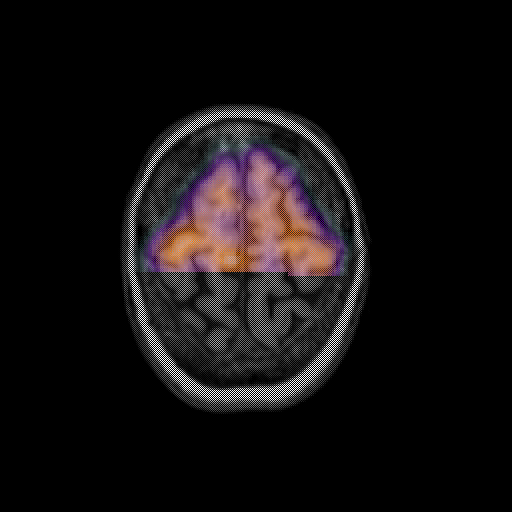

overlay: Slice 45

Slice 45

MRCBFCBF with

T1PDT2T1PDT2